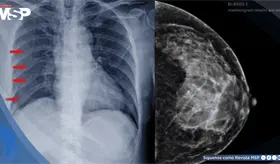

El intenso dolor torácico no fue una recaída ni metástasis, sino un daño óseo provocado por la reirradiación. Los huesos, debilitados por la radioterapia previa y la reirradiación, estaban perdiendo su capacidad de curarse adecuadamente.